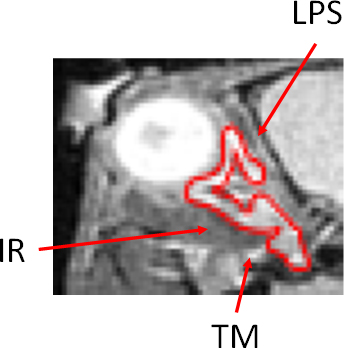

Figure 3 of Lee, Mol Vis 2017; 23:572-578.

Figure 3. An enlarged image from slice 7 of HT-1 in Figure 2. The zoom image illustrates that the software can identify the extraocular muscles as a whole but cannot differentiate among them due to imaging resolution limitations.